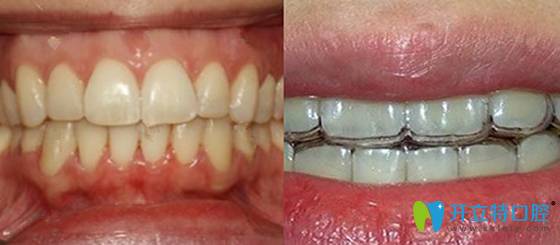

隱性矯正第110天效果圖:

我做隱性矯正三個(gè)月啦,現(xiàn)在的牙齒看上去已經(jīng)很整齊了,門(mén)牙已經(jīng)在慢慢往回緊了,不過(guò)這還不是較終的效果,還要繼續(xù)調(diào)整,那就是說(shuō),效果只會(huì)比現(xiàn)在更好,嘻嘻嘻,灰常開(kāi)心!